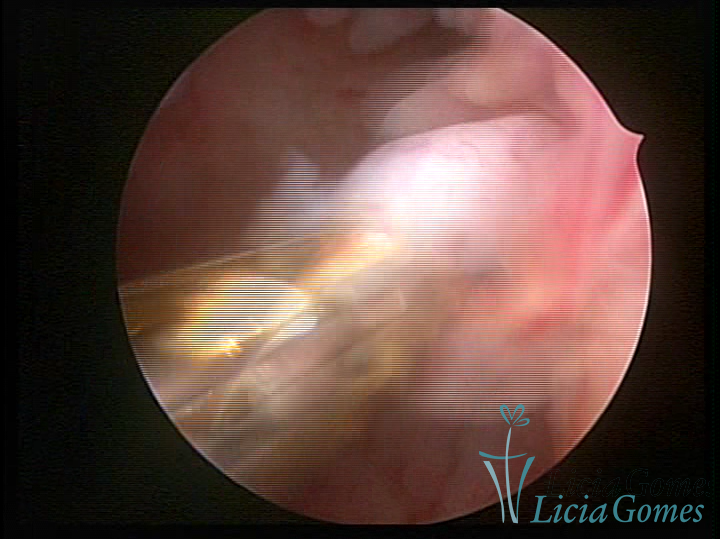

A histeroscopia permite analisar as características da superfície endometrial, não podendo avaliar a profundidade ou o grau de invasão miometrial.

Mas poderá verificar se as lesões são do tipo: focal; regional ou difusa

Este pode apresentar uma gama variável de aspectos macroscópicos, com aspecto pseudopolipoide; lembrando tecido cerebroide ou com reação deciduoide;a vascularização superficial é mais evidente e com vasos em formatos de saca-rolha ou espirais visualizando também a vascularização com atípias, com aumento do calibre dos vasos superficiais, pode ser encontrado também tecido em necrose, poderá haver um pequenos dendritos (papilomatoso).